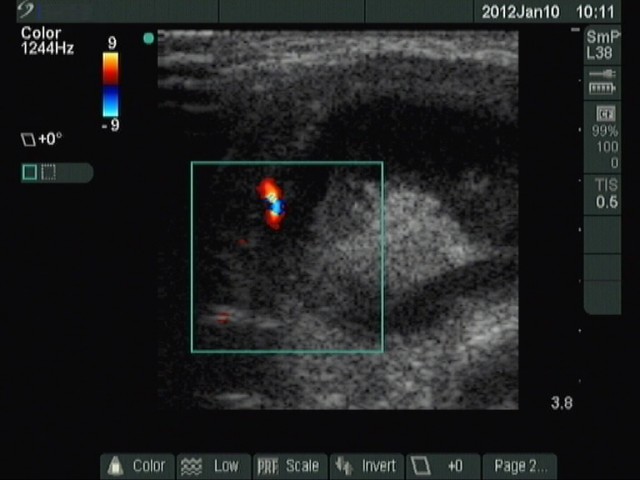

Second row: ultrasonographic picture before the second sclerotherapy. The size of the lesion was 38x28x39 mm (width x depth x length).